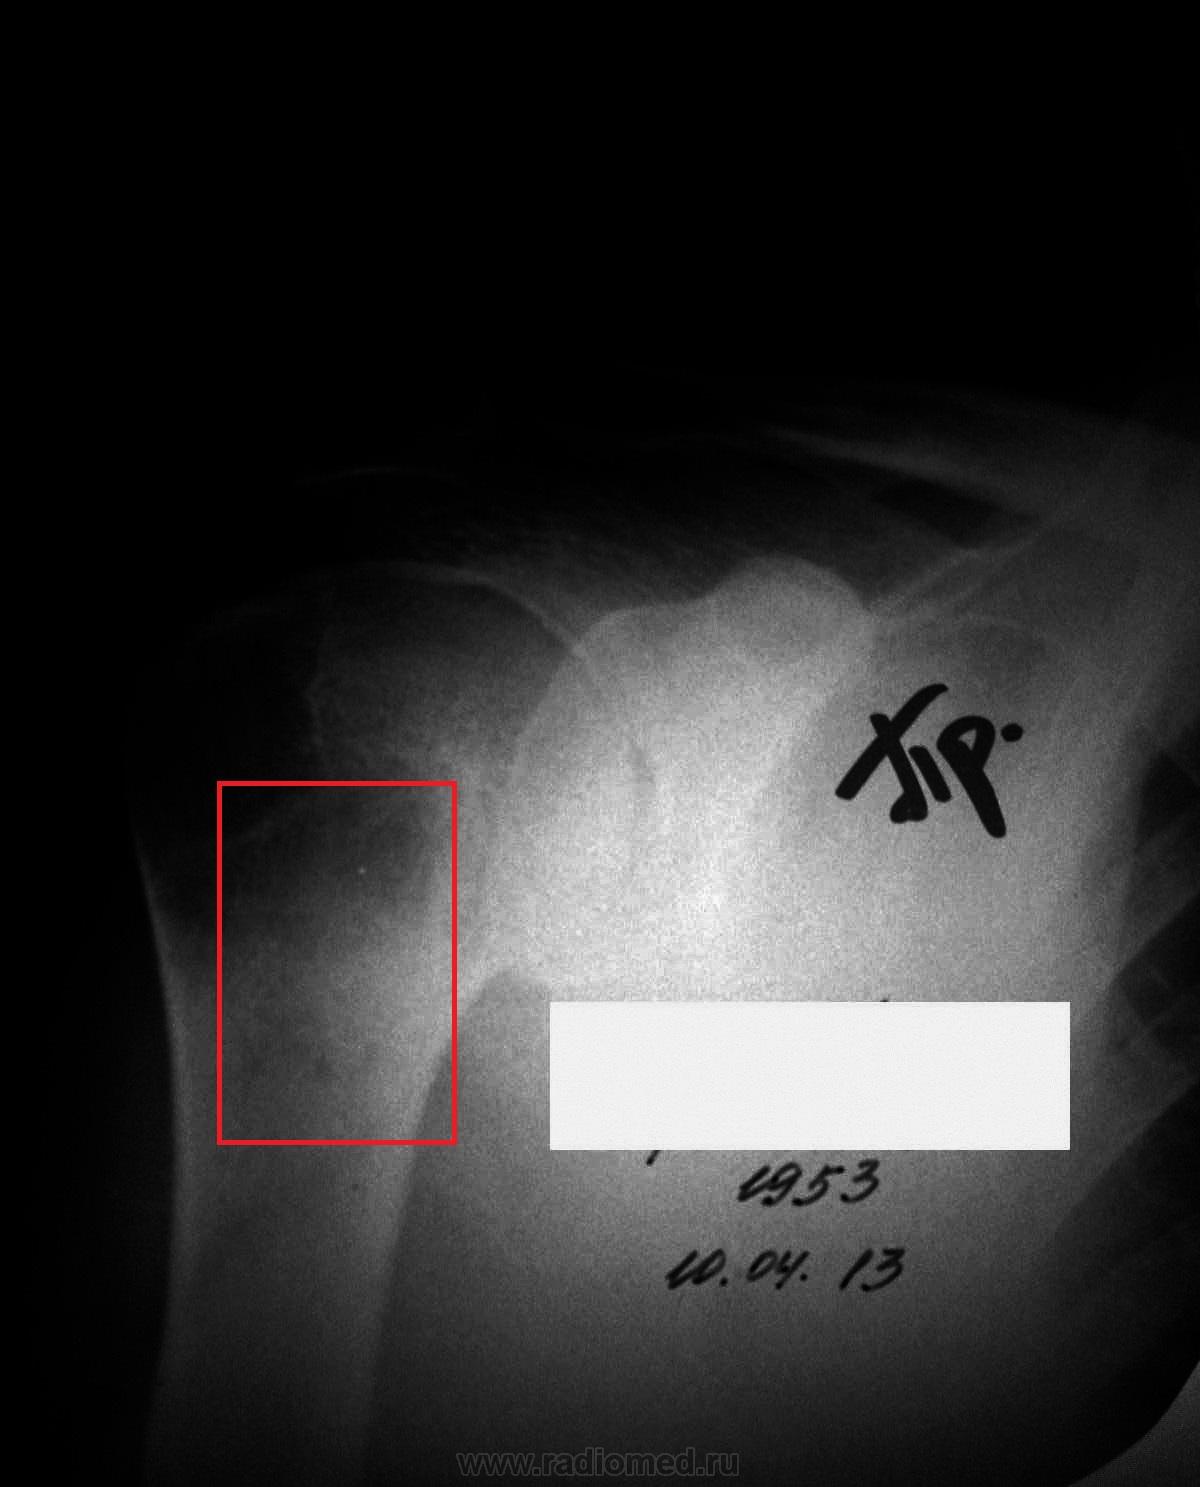

Обратилась женщина на консультацию в онкодиспансер. На руках 1 снимок, его описание и направление от ортопеда.

Заключение рентгенолога: 1) Солитарная хондрома. 2) Доброкачественная хондробластома.

Ортопед-травматолог: Киста головки правой плечевой кости? Асептический некроз головки плеча?

Я вижу участок просветления между большим и малым бугорками и дистальнее мелкие неравномерные участки деструкции. Затрудняюсь интерпретировать.

Благодарю. Возникает еще вопрос: то, что ниже хондробластомы - это некроз или что? (мне кажется, что это деструкция костной ткани).

я сделала контрлатеральную сторону, просветления симметричные. чуть позже выложу фото (как обработаю). в общем, написала: артроз, обызвествления поддельтовидной сумки и остеопороз под вопросом.

Стрелочкой не покажете, плиз?

Нашла в Рентгеноанатомическом атласе скелета (норма, варианты, ошибки интерпретации) Королюка, что в области больших бугорков плечевой кости часто бывает локальный остеопороз. А обызвествления поддельтовидной сумки поторопилась написать, надо было бы вывести на край. Как то так.